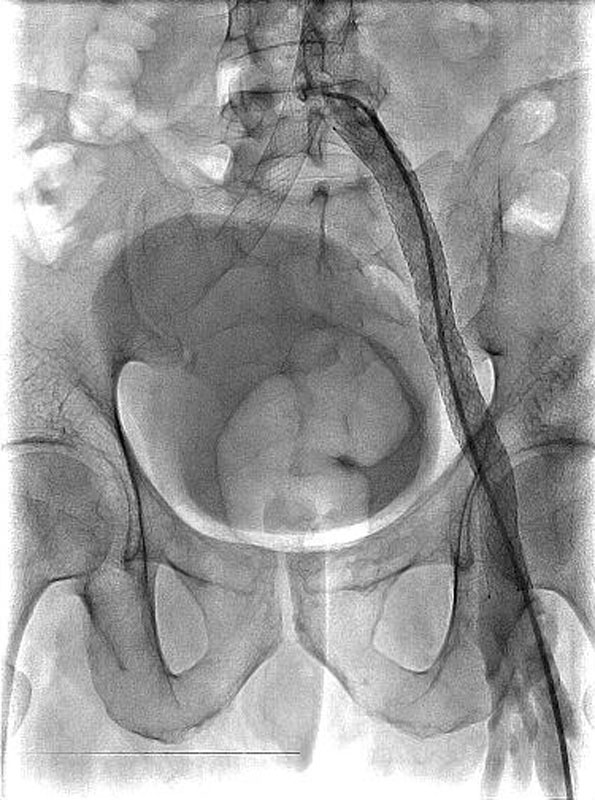

Впервые в России имплантирован венозный стент нового поколения VENOVO, выполнена реканализация и стентирование глубоких подвздошных вен у пациента с синдромом нижней полой вены, развившегося после билатерального илио-феморального тромбоза